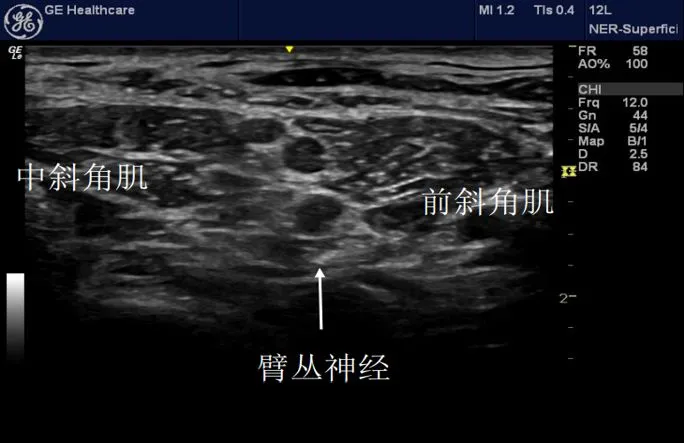

Let's take a look at the image below.

See, if you are not familiar with anatomy, can you quickly and accurately locate the nerve on the ultrasound image? I don't think so. However, if we remember the anatomical structure diagram below, it will be much easier to interpret the ultrasound image above!

For example, in clinical practice, when performing an interscalene brachial plexus block, we identify the anterior scalene muscle, middle scalene muscle, transverse processes of the vertebrae, carotid artery, vertebral artery, and phrenic nerve. By understanding their spatial relationships, we can determine the exact location of each nerve and then proceed with the needle insertion and medication injection.